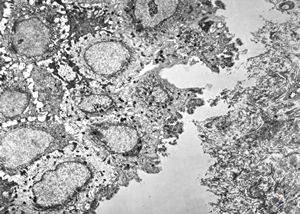

M, 3y. | cutaneous nerve